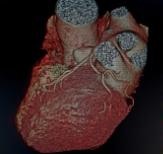

MédicoRadiólogoconsubespecialidadenimágenesdelcorazón

EgresadoporelInstitutoNacionalde CardiologíaIgnacioChávezenlaciu‐daddeMéxico.

Encargadodeldepartamentodeimágenesdel corazón,soyelresponsabledecoordinaral equipodetécnicosenlosprotocolosdeimá‐genescardiacascomoloson:

• Angiotomografíadecorazóncon reconstrucciónen3D

• Calcioscore

• Tomografíadeangiocoronarias

• Resonanciamagnéticadelcorazón

MicolaboraciónconIMAGEN–CDI,es graciasalmilagrodelateleradiología,en dondeatravésdeunaplataformadigitalse puedenrealizarlosestudiosadistancia,dan‐

doindicacionesalmomentoporvideo llamada.Asímismonoshacemosresponsab‐lesdelcontroldecalidad.

EnIMAGEN–CDItenemosmuchocorazón,y queremoscuidareltuyo.

¿QUÉESUNATOMOGRAFÍADECORONARIAS?

Latomografíadecoronariasesunestudio cardiaconoinvasivoqueutilizarayosXpara tomarimágenesdelcorazónyvalorarlaanato‐míadelasarteriascoronarias.

ConlaAngiotacCoronariasepuedentomar imágenesdelcorazónquelate,mostrarcalcio ybloqueosenlasarteriasdelcorazón.

Latomografíacardiacapermitevalorar tambiénlafuerzaconlaquesecontraeelco‐

razón;delamismamaneraqueseevalúacon unecocardiograma.

Enestemismoestudiosepuederealizaruna valoracióncompletadelaaortaparadeterminar siexistenaneurismasodiseccionesdelaaorta.

Cuandosedetectalesióndeltroncodelacoro‐nariaizquierdaocuandohaylesiónde3arterias coronarias;sedebederealizarunacirugíadeby‐passconimplantesdearteriamamariainterna.

Sintintedecontraste,sepuedeusarpara medirlacantidaddecalcioenlasarteriasdel corazón.Supuntajedecalciolesdaalosmé‐dicosunaideadecuántaplacahayenlas arteriasdelcorazónqueaúnnohacausado problemas.Supuntajedecalciopuedeayudar apredecirsuriesgodeataquecardíaco.